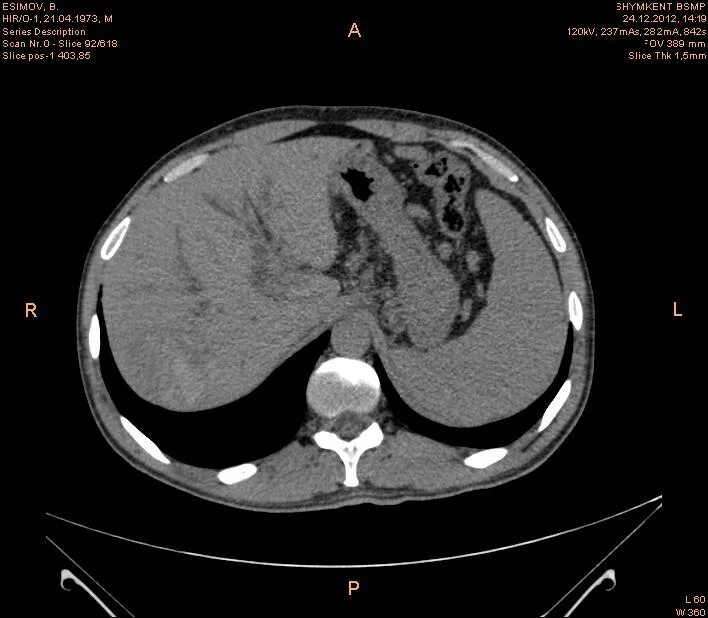

Кт ухта